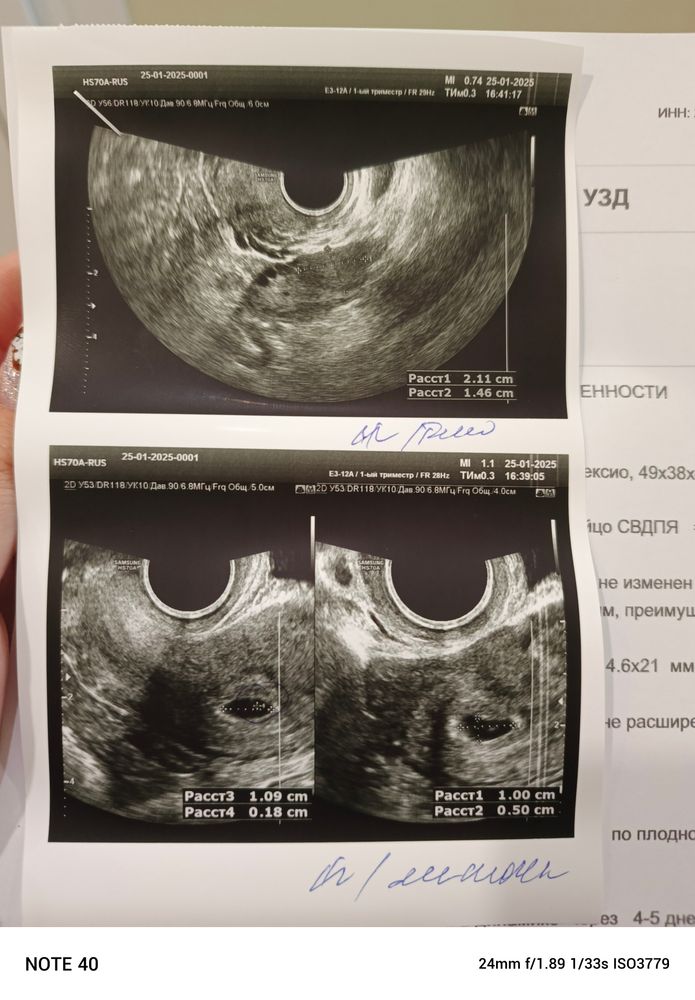

Это ведь не большая отслойка, да?